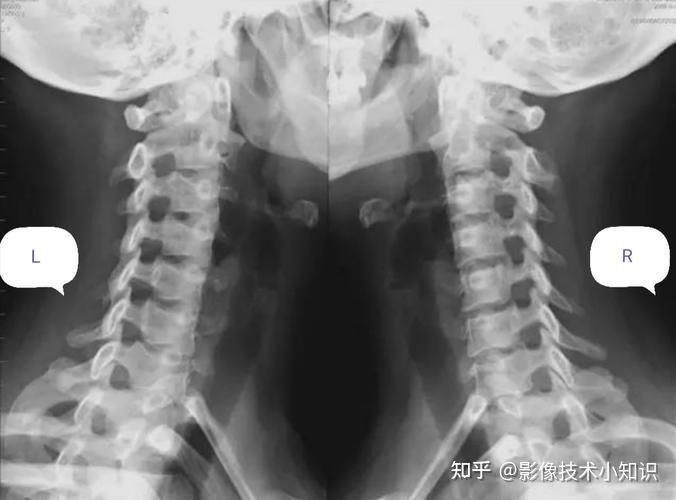

完整颈椎正位,开口看到枕骨大孔和双侧枕骨髁,颞骨乳突,完整的枢椎齿